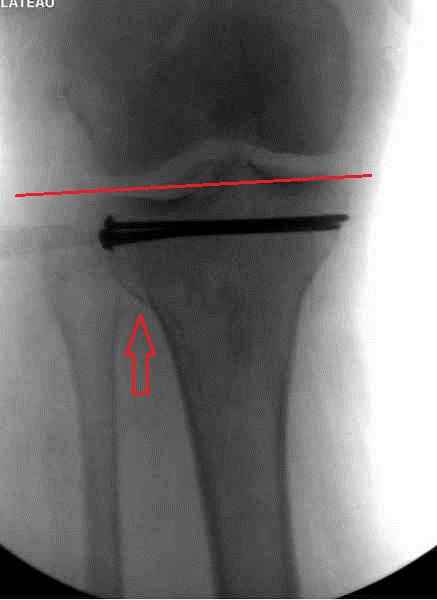

Снимки до и после закрытой репозиции

На представленном после операционном снимке нет репозиции, на что указывает низкое положение тибиального плато и перекрытие кортикальных пластинок в метафизарной части - указано стрелкой. Обычно чрескожную фиксацию я применяю

Пациентки прооперирована, результат чего на снимках. Выполнена открытая репозиция костей правой голени, синтез малоберцевой пластиной, б/берцевой винтами, имеющиеся фиксаторы не подходили, было принято решение репонировать отломки, синтез винтами, гипсовая повязка.

Репозиция внутрисуставных переломов неудовлетворительная и не адекватна.

В лечении переломов пилона восстановление длины малоберцовой является индикатором и ориентиром для успешного лечения. Первый этап восстановления по длине не удался, малоберцовая остается короткой, и репозиция суставной поверхности осталась неудовлетворительной. Длина передней колонны не восстановлена, а в дистальном фрагменте имеется флексия. Оставлена без внимания потеря кости в метафизе. Шурупы 4.5 мм будут выступать после спадения отека, и возможно будут причиной мягкотканого осложнения в гипсе.